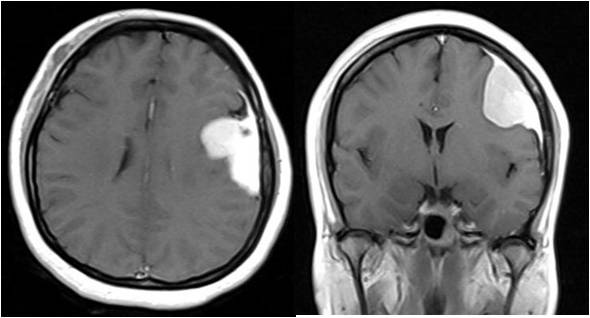

脑膜尾征

mri征象:1,典型的脑膜瘤多变现未等或稍短t1,等或稍长t2信号类圆形